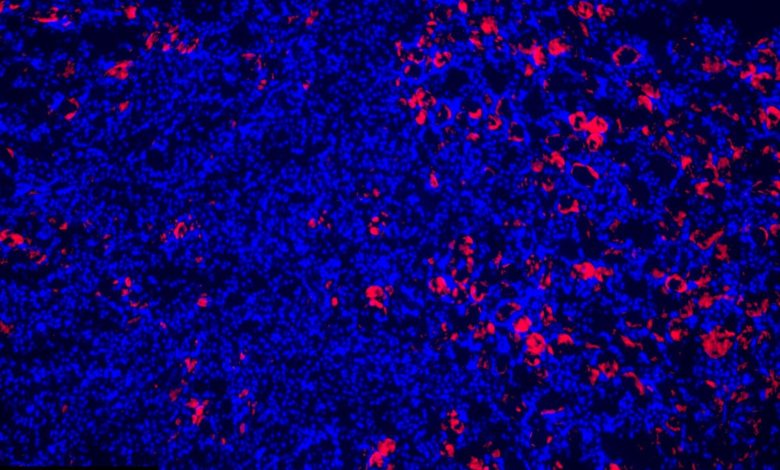

Paradoxalmente, uma variante do gene que aumenta a inflamação também tem um efeito protetor nos rins. Visto aqui, núcleos de células renais (azul) e um influxo de células reguladoras do sistema imunológico (rosa) que evitam danos em um rim lesionado. Crédito: Garvan

Pesquisadores do Garvan Institute of Medical Research, University of New South Wales, Sydney e Westmead Hospital, descobriram que variantes genéticas comuns de TNFAIP3que aumentam a inflamação no corpo, podem, paradoxalmente, proteger os rins de danos a curto prazo.

“Apesar do aumento da inflamação, esta variante rara surpreendentemente protegeu os rins de lesões. Descobrimos que essa proteção se deve a outra função do A20: impedir que as células se autodestruam”, diz a professora Natasha Rogers, nefrologista e chefe de transplantes do Hospital Westmead, que co-liderou o estudo.